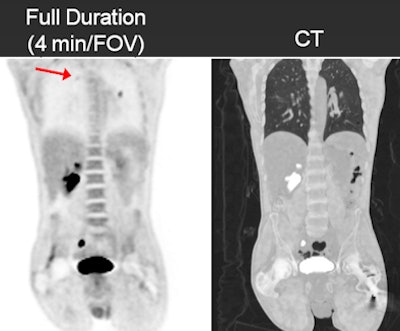

![]() |

| In these images of a 125-lb patient, the half- and full-duration studies had the same findings, whereas there was a false negative in the upper right lung on the quarter-duration scan. |

The analysis found that the one-minute and two-minute scans did not change staging in any patient, compared with the full-duration scan. The two-minute study had identical specificity to the full-duration scan and four false-negative results in two patients, who had a total of more than seven lesions. Sensitivity was 98%, with a specificity of 100%.

The one-minute study failed to detect lesions in 12 patients, compared with the full-duration scan. In total, it produced nine false positives and nine false negatives. Sensitivity was 91% and specificity was 93%.